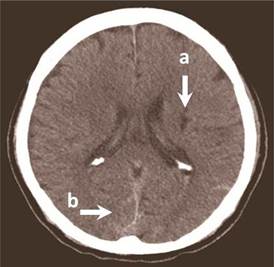

Tomografía axial computarizada de cráneo 64 cortes (Figura 1): se apreciaron imágenes sugerentes de infarto cerebral isquémico antiguo y HSA occipital bilateral Fisher 3.